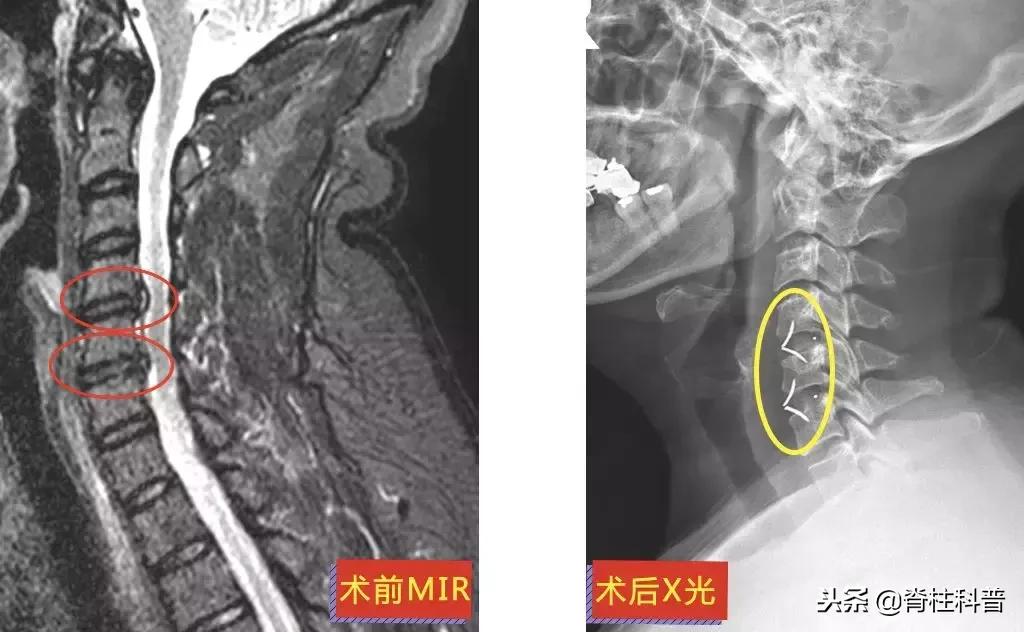

这10多年来,李三姨的左颈、肩背部反复酸痛,休息、热敷甚至是止痛药治疗时可缓解。但是来院就诊前1个月,突然出现左上肢放射性疼痛,于是在2018年8月28日前往当地医院诊治。医生予以中药、针灸治疗,但无效。

10天后,再次予以颈椎牵引治疗,症状稍缓解,可是颈痛发作频繁。经过熟人介绍,特意从茂名来到广州南方医科大学第三附属医院,找到张忠民主任医师治疗。在2018年9月20日在门诊被主任以“神经根型颈椎病”收治入院。10月3日手术,术后疼痛症状得到明显改善。

▲ 李三姨:术前MRI与术后X光